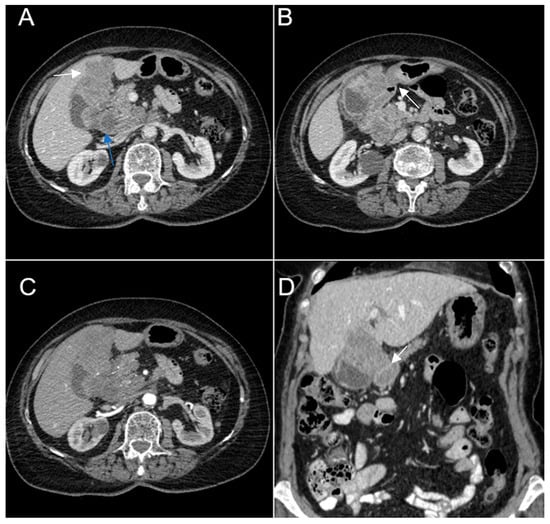

Figure 9. Multiplanar sections of contrast-enhanced CT acquisitions richly illustrating gallbladder carcinoma. (AD). A large, inhomogeneous pseudonodular mass with heterogeneous contrast enhancement, with invasion in the adjacent liver, pyloric antrum and duodenum II (white arrows). (A) Lymphatic metastases; with compressive effect on the inferior vena cava and right renal artery and vein (blue arrow).

A 67-year-old female patient with a past medical history of hypertension and autoimmune thyroiditis presented to the Emergency Department with abdominal pain accompanied by nausea and weight loss. Physical examinations revealed abdominal tenderness with a palpable mass in the right hypochondrium. Blood sample demonstrated elevated inflammatory markers, hypochromic microcytic anemia, hepatic cytolysis and increased levels of CEA (12.5 ng/mL) and CA 19-9 (51 U/mL). Contrast-enhanced emergency CT (Figure 9) showed a large mass with heterogeneous enhancement, measuring 94/57 mm, that partially replaced the gallbladder and invaded the liver (segment IVb), pyloric antrum and duodenum II. Bulky celiac and mesenteric lymphadenopathies with areas of necrosis, measuring up to 27/25 mm were present.